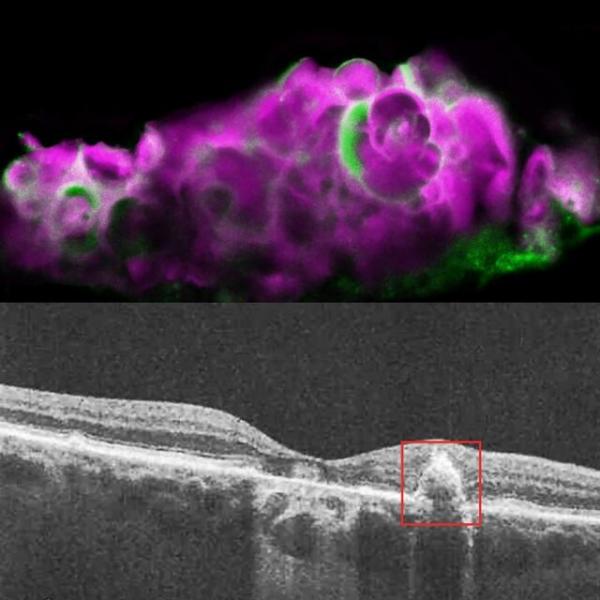

دکتر" گرام ویستو"( Graeme Wistow)، از نویسندگان این پژوهش بیان کرد:ما توانستیم با استفاده از یک مدل ساده کشت سلولی در چشم، نشان دهیم که آملوتین، تحت فشار فعال می شود و نوعی کلسیم را شکل می دهد که معمولاً شبیه آن، در استخوان و دندان دیده می شود. زمانی که ما چشم افراد مبتلا به دژنراسیون ماکولای خشک را بررسی کردیم، همین نوع کلسیم را دیدیم.

محققان در بررسی های گذشته خود، یک ترکیب معدنی موسوم به" هیدروکسیل آپاتیت"( HAP) را در چشم بیماران مبتلا به دژنراسیون ماکولای خشک یافتند. هیدروکسیل آپاتیت، یک ترکیب اصلی در مینای دندان و استخوان است.

پژوهشگران، هیدروکسیل و آملوتین را فقط در چشم افراد مبتلا به دژنراسیون ماکولای خشک یافتند. آملوتین هم صرفا در قسمت هایی وجود داشت که فاقد مواد خارج سلولی انباشته شده موسوم به" دروسن"( Drusen) بودند.